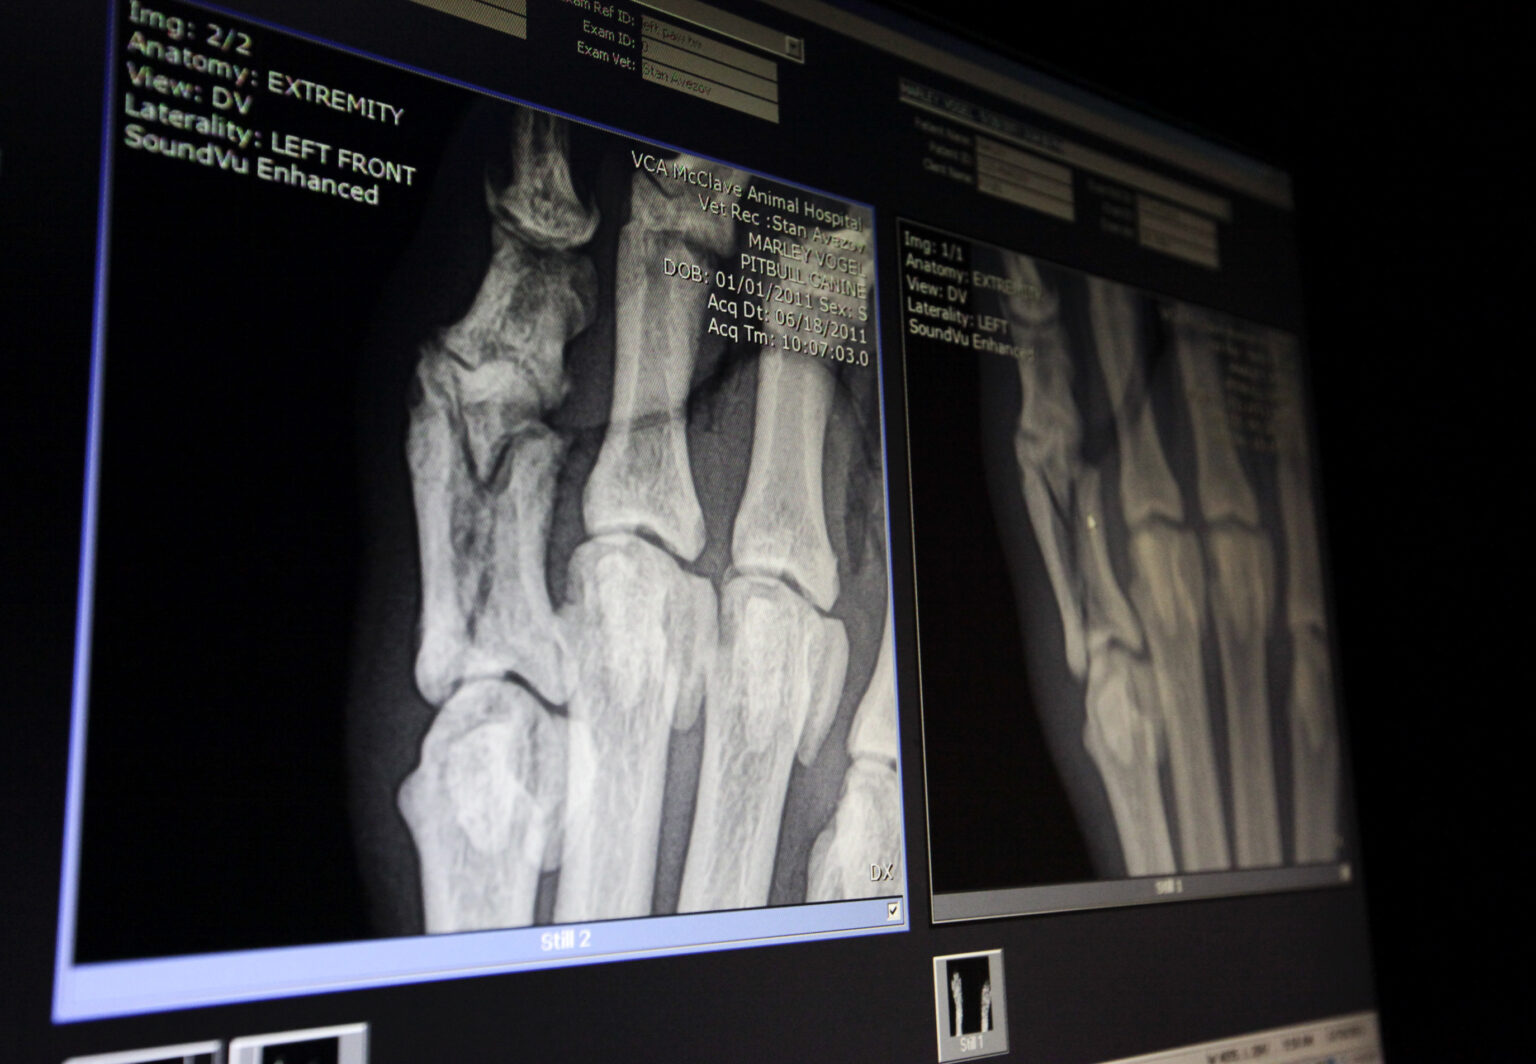

C’est une véritable révolution pour la médecine si elle se confirme ! Des chercheurs chinois affirment avoir développé une colle osseuse révolutionnaire capable de réparer les fractures en seulement trois minutes grâce à une simple injection. Cette innovation promet de réduire la dépendance aux implants métalliques et aux interventions chirurgicales lourdes, offrant une solution rapide et moins invasive pour le traitement des fractures.

Le produit, surnommé Bone-02, est injecté directement dans la fracture via une fine incision de 3 cm. En moins de trois minutes, il lie les fragments osseux avec une force de plus de 400 livres, permettant une fixation solide et précise. Contrairement aux plaques métalliques, cette colle est biodégradable, se résorbant naturellement au fur et à mesure de la guérison osseuse, sans nécessiter d’intervention pour retirer des implants.

Des tests sur plus de 150 patients ont montré que Bone-02 offre une fixation stable, réduit le risque d’infection et accélère la guérison par rapport aux méthodes traditionnelles. Dans certains cas de fractures du poignet, la guérison complète a été observée en seulement trois mois, sans complications ni besoin d’une chirurgie supplémentaire.